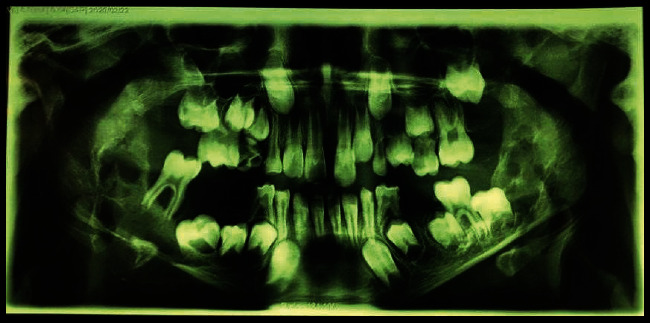

Central giant cell granuloma (CGCG) is considered a benign intraosseous lesion with a varied range of clinical features in two subtypes, including aggressive and non-aggressive lesions. This study presents a 9-year-old boy with multiple bilateral CGCG in the mandible without any systemic disease or specific syndrome. Clinical, radiographic, and histopathological findings demonstrated the aggressive lesions. It is discussed how the differential diagnosis and treatment can be determined based on the patient's age as well as the size and manner of the lesion.

Abstract Image